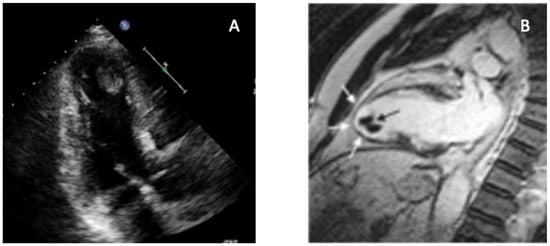

The most frequent cause of apical obliteration is apical thrombosis, a type of left ventricular thrombosis (LVT) marked by the formation of a blood clot inside the apical cavity. It has significantly higher risks of systemic embolism, stroke, cardiovascular events, and death. It is usually caused by blood stasis in severe ventricular systolic dysfunction of both ischemic and non-ischemic etiologies [34]. Up to 15% of patients with STEMI, 25% of patients with anterior STEMI, and 2–36% of patients with non-ischemic cardiomyopathies experience LVT [34]. Large anterior infarction, severe left ventricular dysfunction, microvascular obstruction (MVO), and delayed reperfusion are important predictors of this occurrence [35]. TTE represents the first-line screening method because of its accessibility and quick acquisition, even though sensitivity remains low [36]. Apical visualization may be limited by near-field clutter, foreshortening, and suboptimal acoustic windows. Standard diagnostic criteria include a mass with distinct echogenicity, well-defined margins, visualization in at least two orthogonal views, and contiguity with an akinetic or dyskinetic segment [35]. Additional echocardiographic markers of stasis, such as reduced apical longitudinal strain or a low E-wave propagation index (EPI < 1), have shown good sensitivity but limited specificity for thrombus detection [35]. Contrast TTE significantly improves endocardial border delineation and LV cavity opacification, frequently doubling thrombus detection compared with non-contrast TTE, particularly for mural or laminated thrombi [37,38]. CMR is the gold standard for apical LVT detection due to superior spatial resolution and unique tissue characterization potential [39]. Thrombus appears as a hypointense, non-enhancing mass on LGE imaging; long-inversion-time sequences (~600 ms) markedly improve conspicuity and outperform cine imaging [35]. These findings are consistent with multicenter data and meta-analytic evidence demonstrating the superior sensitivity of CMR over TTE for LVT detection [35,40]. CMR is especially useful for detecting small, mural, or laminated thrombi frequently missed by echocardiography [40]. LGE burden strongly correlates with thrombus formation, with ischemic cardiomyopathy demonstrating a fivefold increased prevalence compared with non-ischemic disease [41,42]. CMR also differentiates thrombus from MVO, the latter being intramyocardial and surrounded by hyperenhancement [7]. Emerging tools—including targeted contrast agents and 4D flow MRI—may further refine thrombus characterization and risk prediction [9,43]. Cardiac CT angiography (CCTA) offers high spatial resolution and rapid acquisition when CMR is contraindicated [29]. Its utility is balanced by radiation exposure and the need for iodinated contrast. Thrombus is distinguished from apical hypertrophic cardiomyopathy, endomyocardial fibrosis (EMF), and tumors by its avascular and non-enhancing profile. Heterogeneous enhancement suggests tumor, whereas subendocardial fibrosis or calcification are more typical of EMF. Since prompt anticoagulation for at least three months lowers embolic risk and may affect long-term outcomes, early and accurate identification of LVT is crucial. Radiation exposure and need for iodinated contrast represent important limitations. Moreover, comparative data with CMR are still limited [35]. The multimodality appearance of apical LVT, including the distinction between non-enhancing thrombus and surrounding dyskinetic myocardium, is shown in Figure 1.

Figure 1. Multimodality imaging of left ventricular apical thrombus. Key teaching point: Combining contrast-poor echocardiography with CMR allows definitive differentiation between apical thrombus and other causes of apical obliteration such as ApHCM, EMF, or LVNC. (A) Transthoracic echocardiography (apical four-chamber view) demonstrates a well-defined, hyperechoic mass adherent to the LV apex, associated with severe regional wall-motion abnormality. (B) CMR cine imaging confirms an apical thrombus (black arrow), visualized as a non-enhancing, low-signal mass sharply distinct from the surrounding dyskinetic myocardium (white arrows). Multimodality evaluation enables confident identification of apical LVT and prevents misdiagnosis as hypertrophic, infiltrative, or fibrotic apical disease, directly guiding anticoagulation and clinical management. Original image from our institution (single patient).